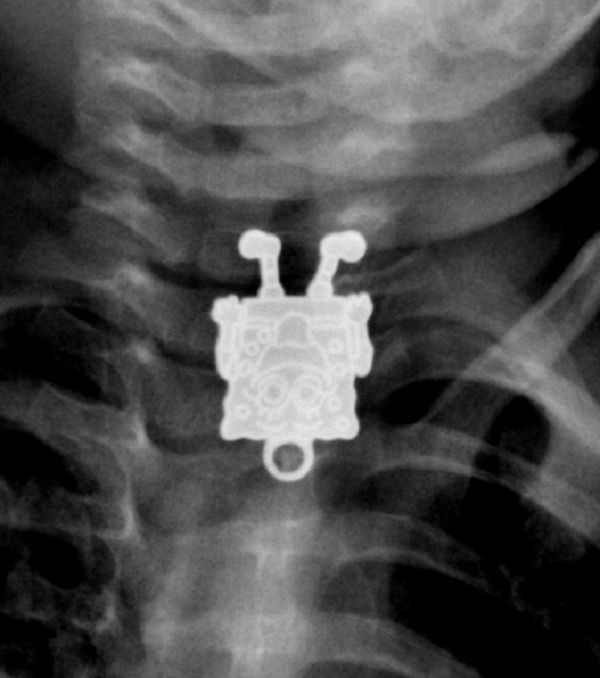

/ 15SpongeBob

Obraz

© imgur.com

Widać, to ulubiona postać z kreskówek tego dziecka.